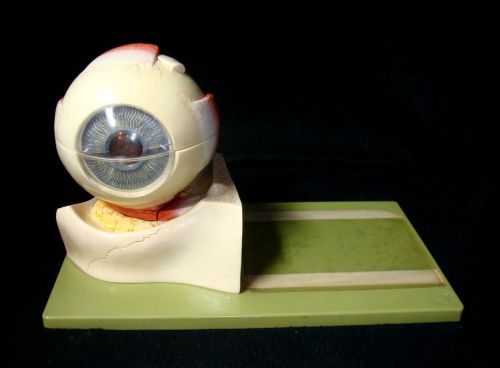

SOMSO CS1 Human Eyeball Anatomical Eye Model - 5 parts CS 1